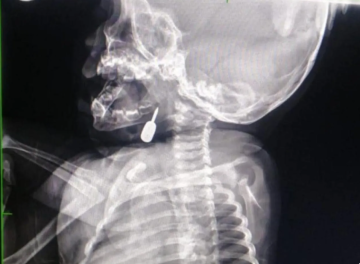

تمكّن أخصائي الأنف والأذن والحنجرة الدكتور محمود السبول من إجراء عملية _فتح رغامى_ تُعد الأولى من نوعها في مستشفى الملكة رانيا العبدالله، وقد تمت بنجاح.

وفي تدخل طبي عاجل، أنقذ الدكتور السبول حياة طفل يبلغ من العمر أحد عشر شهراً، بعد أن وصل إلى قسم الطوارئ وهو يعاني من حالة اختناق حادة نتيجة وجود جسم معدني عالق في منطقة الحنجرة. وقد تم استخراج الجسم بنجاح، مما أسهم في إنقاذ حياة الطفل.